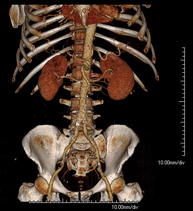

- TC Abdominopélvico Prueba diagnóstica que consiste en obtener imágenes bi y tridimensionales del abdomen y de la pelvis de alta definición anatómica (estructuras óseas, estructuras vasculares, hígado, páncreas, vesícula biliar, riñones, glándulas suprarrenales, bazo, intestino delgado y grueso, vejiga, útero y ovarios, próstata y vesículas seminales, uréteres, etc.) mediante el empleo de un equipo de TC (Tomografía Computarizada). La mayoría de estudios requieren el empleo de contraste yodado. Prueba diagnóstica que consiste en obtener imágenes bi y tridimensionales del abdomen y de la pelvis de alta definición anatómica (estructuras óseas, estructuras vasculares, hígado, páncreas, vesícula biliar, riñones, glándulas suprarrenales, bazo, intestino delgado y grueso, vejiga, útero y ovarios, próstata y vesículas seminales, uréteres, etc.) mediante el empleo de un equipo de TC (Tomografía Computarizada). La mayoría de estudios requieren el empleo de contraste yodado.